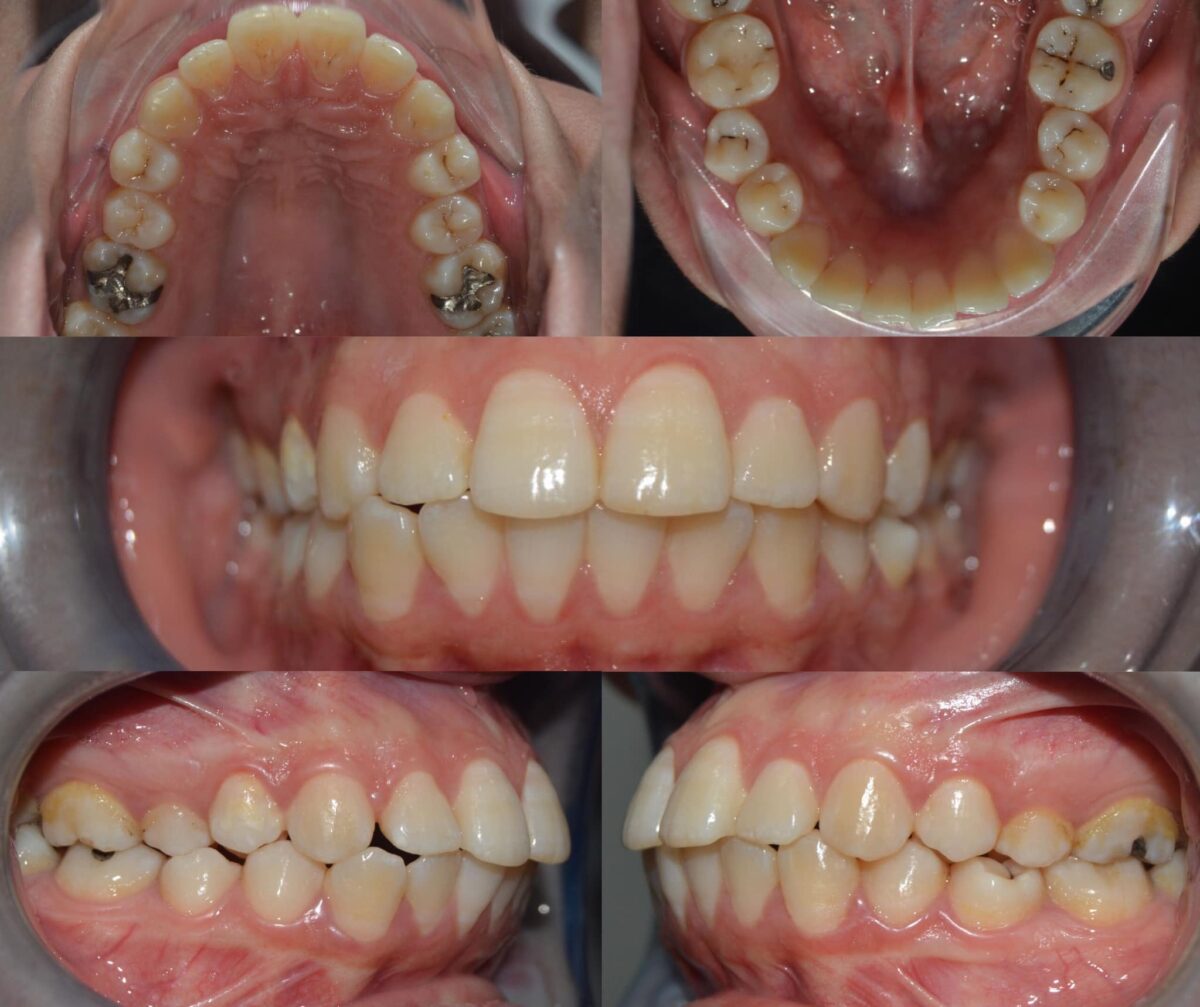

دكتور أحمد مجدي بيبدأ معاك بفحص شامل للأسنان واللثة، باستخدام أحدث الكاميرات اللي بتصور الفم من جوه وتعرض الصورة على شاشة قدامك، بحيث تشوف بنفسك المشاكل اللي محتاجة علاج. ولو الحالة تتطلب، بيعملوا أشعة بانورامية أو ثلاثية الأبعاد بتوضح أدق التفاصيل، وده بيساعد على وضع خطة علاجية دقيقة وفعالة. الأسلوب دا بيخليك شريك في قرار العلاج وفاهم كل خطوة قبل ما تبدأ.

للي محتاجين تقويم، سواء معدني أو شفاف، العيادة بتوفر أحدث حلول التقويم المناسبة لكل حالة، مع متابعة دورية لضمان تقدم العلاج بالشكل المطلوب. وكمان لو في فقدان سن، بيتم تعويضه بزرعات أسنان من التيتانيوم المعتمد دوليًا بعد فحص شامل لعظام الفك وأشعة دقيقة، لضمان أفضل ثبات ونتيجة تدوم سنين.